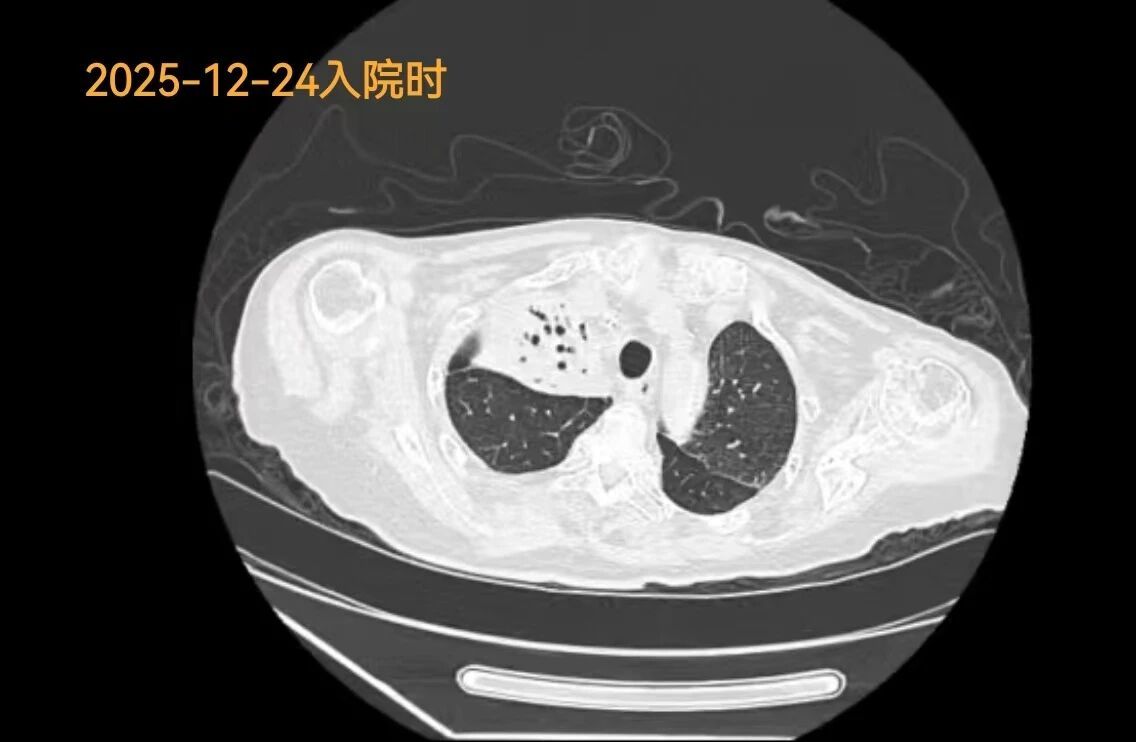

3、新疆医院多学科联手完成高难度经皮肺穿刺

近日,新疆医院呼吸与危重症医学科、胸外科、放射影像中心联手,完成1例高难度经皮肺穿刺活检术。手术经过影像科精准定位,呼吸与胸外科医生在CT引导下,以毫米级的精度调整进针角度与深度,避开“红线”,直取病变核心,最终抵达目标,成功取材。